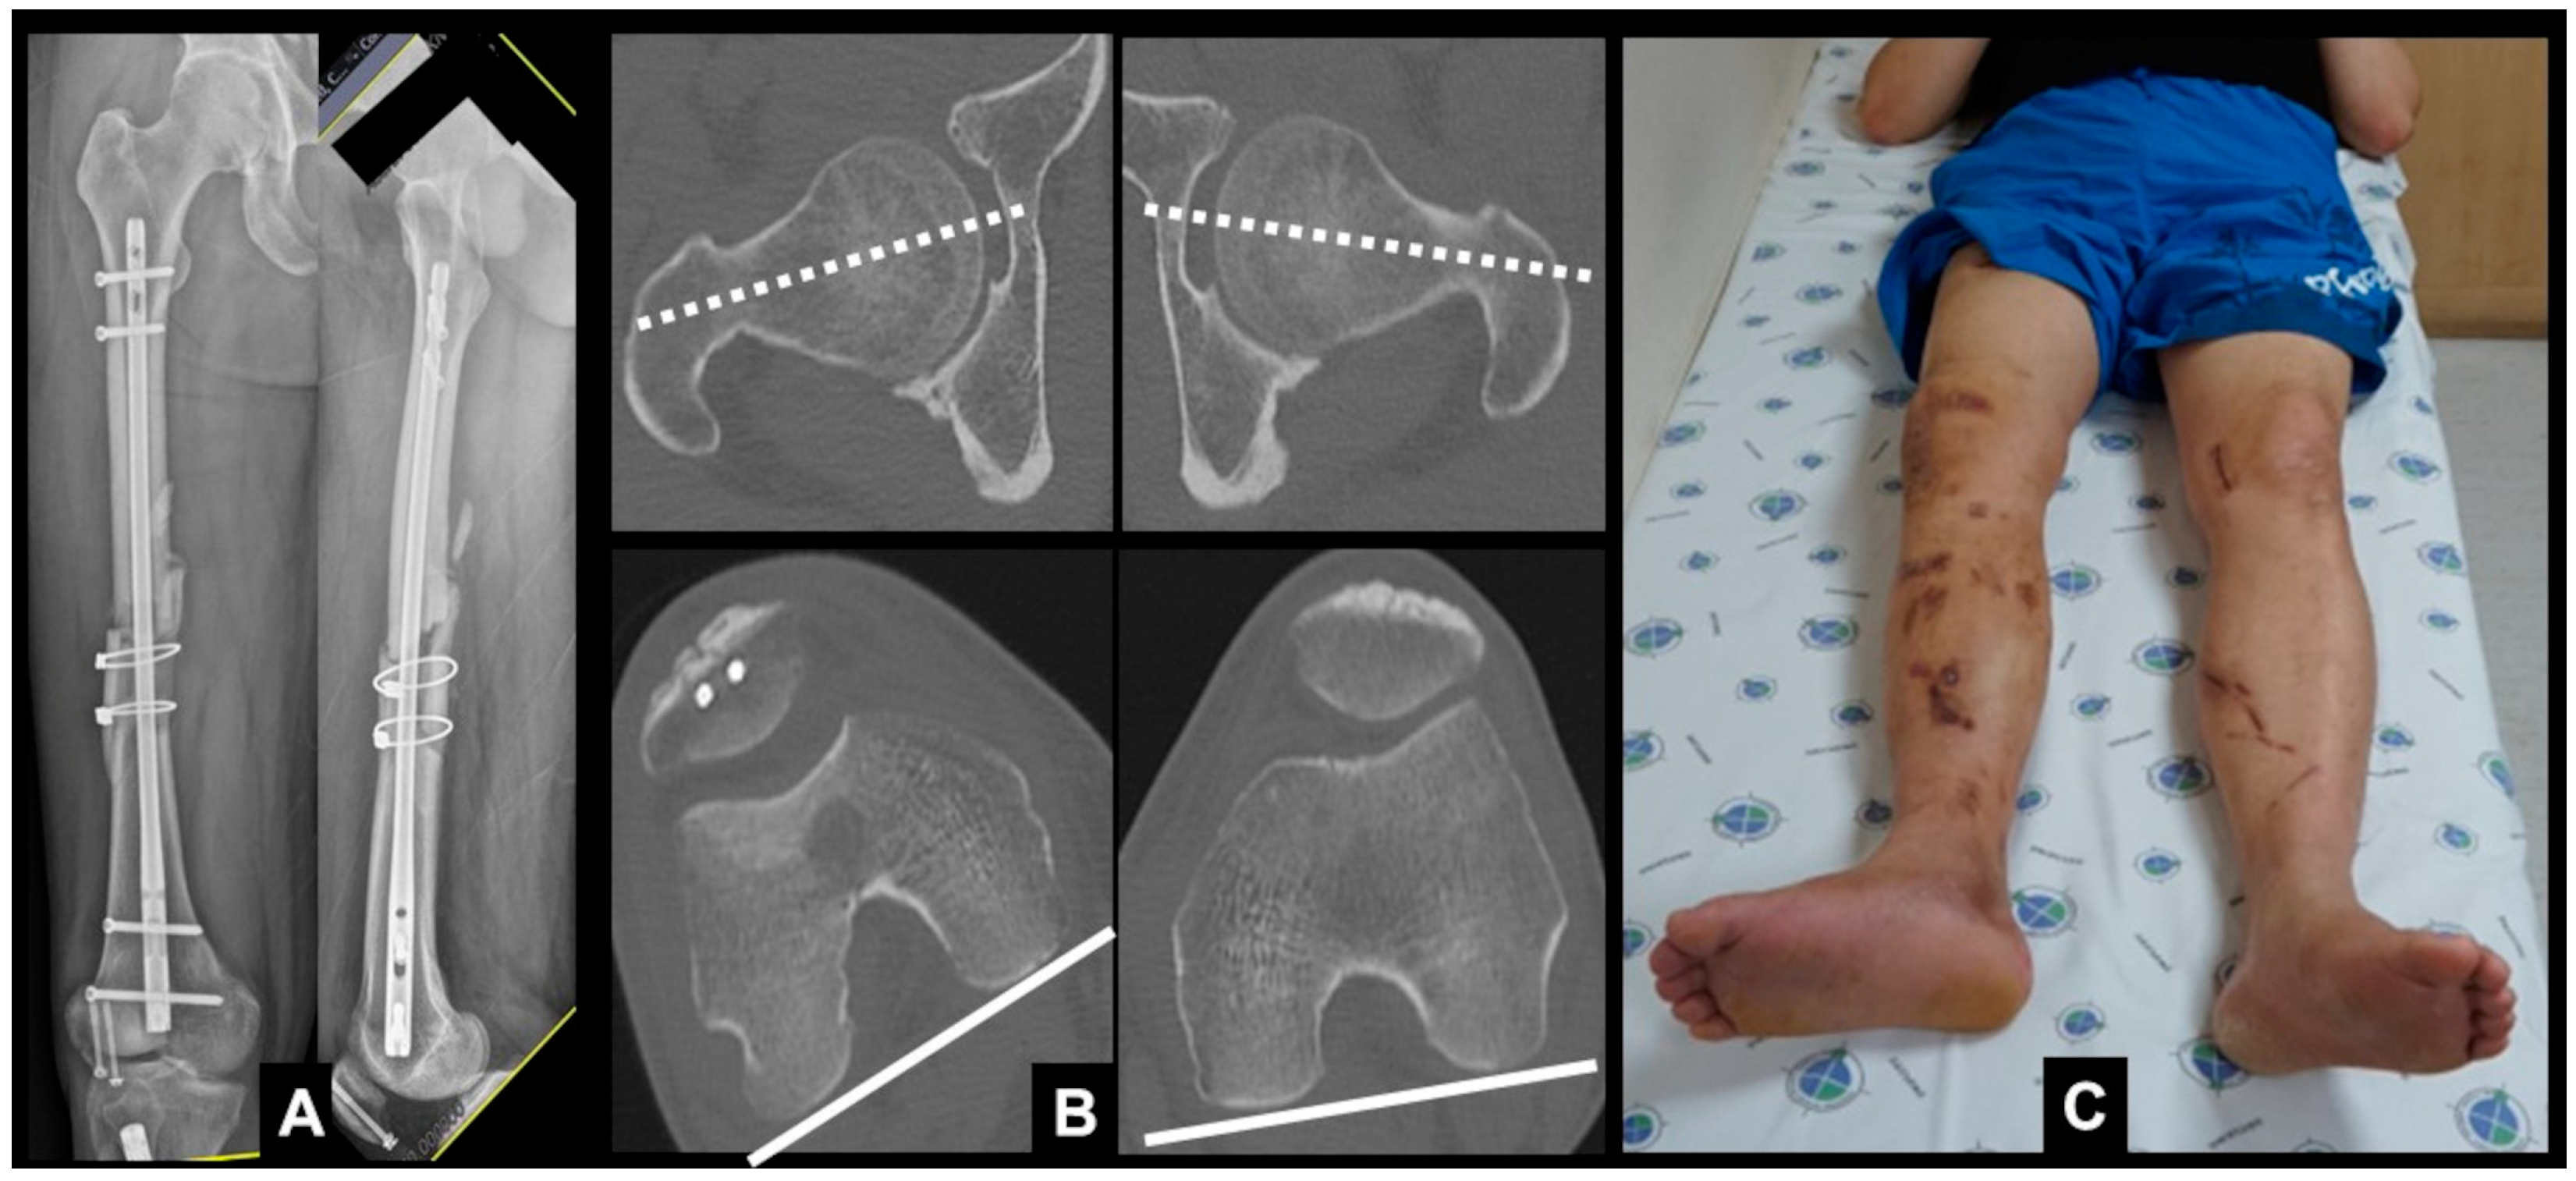

| No. | Sex | Age (Year) | Location | Cause | Rotational Deformity | Associated Deformity | Implant | Bone Graft | Pre- Operative Difference | Angle Measured Using SP App | Post- Operative Difference | Gained Angle | Time to Union (Weeks) |

|---|---|---|---|---|---|---|---|---|---|---|---|---|---|

| 1 | M | 15 | Femur | Malalignment | Internal | Nail | none | 16.1 | 15.8 | 2.3 | 13.8 | 12 | |

| 2 | M | 37 | Femur | Nonunion | External | Nail | YES | 38.3 | 36.1 | 3.2 | 35.1 | 16 | |

| 3 | M | 22 | Femur | Malalignment | External | Nail | none | 22.3 | 20.9 | −1.5 | 23.8 | 16 | |

| 4 | M | 49 | Femur | Malunion | External | Varus | Nail | YES | 15.6 | 14.1 | 1.4 | 14.2 | nonunion |

| 5 | F | 32 | Femur | Nonunion | Internal | Nail | YES | 27.8 | 29.5 | 4.3 | 23.5 | 18 | |

| 6 | M | 50 | Femur | Malunion | Internal | Varus | Plate | none | 20.2 | 20.3 | −2.1 | 22.3 | 16 |

| 7 | M | 57 | Femur | Nonunion | External | Nail | none | 20 | 19.2 | −4.2 | 24.2 | 18 | |

| 8 | M | 70 | Femur | Nonunion | External | Nail | YES | 35.9 | 35.3 | −3.3 | 39.2 | 20 | |

| 9 | M | 57 | Femur | Nonunion | Internal | Nail | YES | 23.5 | 22.2 | 2.5 | 21 | 24 | |

| 10 | M | 58 | Femur | Nonunion | External | Nail | YES | 11.2 | 10.4 | −2.7 | 13.9 | 20 | |

| 11 | M | 46 | Femur | Nonunion | External | Nail | YES | 23.9 | 23.4 | 4.8 | 19.1 | 18 | |

| 12 | M | 11 | Femur | Malalignment | External | Nail | none | 20.6 | 20.1 | −1.6 | 22.2 | 14 | |

| 13 | M | 27 | Femur | Nonunion | Internal | Nail | none | 21.8 | 20.5 | 4.2 | 17.6 | 18 | |

| 14 | M | 24 | Femur | Malunion | Internal | Varus | Nail | none | 17.8 | 19.6 | 3.0 | 14.8 | 16 |

| 15 | F | 15 | Tibia | Malalignment | Internal | Procurvatum | Plate | none | 16.3 | 14.7 | 1.3 | 15 | 14 |

| 16 | M | 77 | Femur | Nonunion | External | Nail | none | 23.1 | 20.2 | 4.6 | 18.5 | 20 | |

| 17 | M | 17 | Femur | Nonunion | External | Nail | YES | 17.2 | 15.9 | 2.5 | 14.7 | 20 | |

| 18 | M | 20 | Tibia | Malunion | External | Nail | none | 30.3 | 32.5 | 1.5 | 28.8 | 20 | |

| 19 | M | 36 | Femur | Nonunion | Internal | Nail | none | 22.1 | 19.3 | −1.8 | 23.9 | 18 | |

| 37.9 | 22.3 | 21.6 | 2.3 | 21.3 | 17.7 |